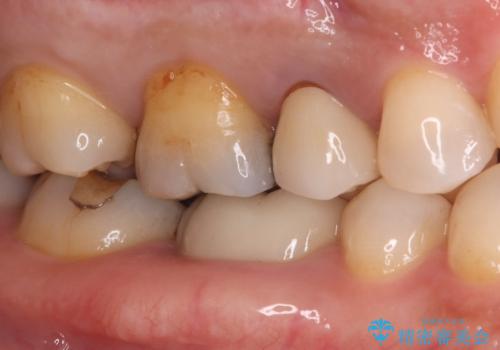

- 長年使用してきた奥歯の古い銀歯のやりかえを主訴にご来院されました。診査の結果、銀歯の下の歯質が薄くなっている部分があり、今後強い力が加わると歯が割れてしまう(破折)リスクが高いと判明しました。このリスクを回避し、歯を長期的に守るため、歯全体をしっかり覆う**セラミッククラウン(被せ物)**による修復を提案。機能的な強度と自然な見た目の両立を目指しました。

治療では、まず古い銀歯を慎重に取り外し、内部の虫歯の有無を確認しました。その後、残っている歯質を保護し、強度を高めるために、適合性に優れたオールセラミッククラウンを作製・装着しました。